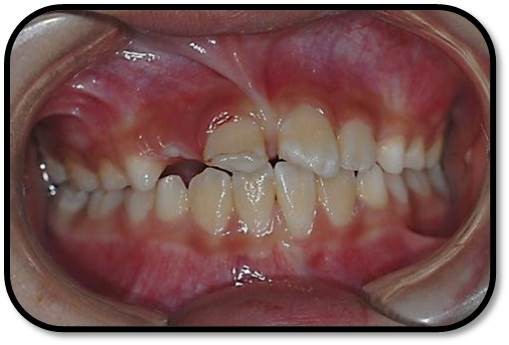

11牙冠龈1/3折断,牙髓暴露约6×1mm2,灰紫色,略有增生,叩(±),不松,龈未见异常,

21牙冠龈1/3釉质横形隐裂,叩痛(-),不松,冷测同正常对照牙,龈未见异常;

11、21正中牙合及前伸牙合未见明显牙合创伤;

11冠折露髓

21外伤牙隐裂

处理:11去旧充填体,11及断片牙体预备(颊侧备斜面,髓腔备固位形,舌侧备排溢道),one-coat bond+纳米树脂粘接断冠,调牙合,抛光。